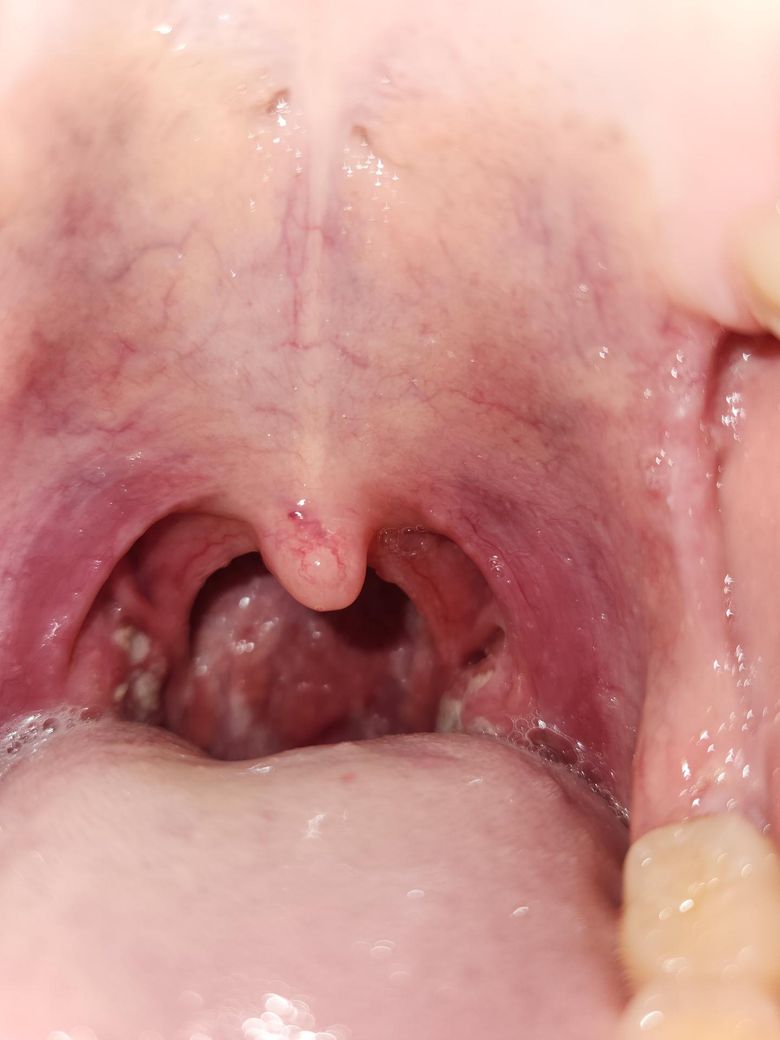

편도결석/편도 세균성감염 상태입니다. 현재 병원을 방문하기 어려운 상태인데 집에서 1주일 정도 가능한 조치가 있을까요?

원래도 편도가 커서 조금만 부어도 이차증상이 매우 잘 나타나는 편입니다.

이틀 전 코막힘이 있는 상태로 취침하여 입을 벌린 채 수면하였고 그 뒤로 편도결석이 생김에 따라 열이 나고 어지러움 등의 증상이 계속 나타나고 있습니다.

• 1번 째 사진